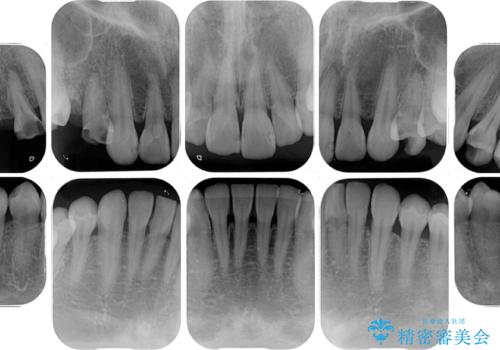

- 奥歯に問題が多くて困っているとのことで来院された患者様です。

開咬により奥歯のみが接触している状態で、前歯部にほとんど接触のない状態で、奥歯に非常に負担のかかる咬み合わせでした。

また、欠損や根管治療の必要な歯など、むし歯による問題も多く散見されました。

まずはむし歯の治療を行い、その後ワイヤー矯正にて咬み合わせを改善し、途中インプラント埋入を行い、矯正治療後に補綴治療を行うこととしました。